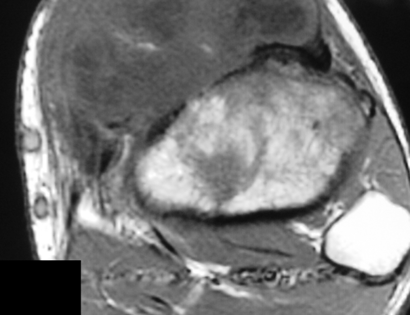

MRI of a Periosteal Osteosarcoma

This image shows a MRI of a Periosteal Osteosarcoma. It is a large mass on the left side of the photo.